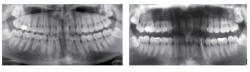

‘셀프 치아장치’로 인한 교합변화 부작용 유발 사례.대한치과의사협회(회장 박태근)가 검증되지 않은 '셀프 치아장치' 사용으로 인해 구강건강에 심각한 문제가 발생하고 있다며 주의를 당부했다.3일치협에 따르면 최근 일부 온라인 쇼핑몰에서는 이갈이, 코골이 방지, 치아교정 등을 목적으로 치과의사 진단 없이 소비자가 직접 사용할 수 있는 마우스피스를 판매하고 있다. 하지만 이와 같은 셀프 치아장치는 효과가 입증되지 않았을 뿐 아니라 오히려 다양한 부작용 사례가 보고되고 있어 각별한 주의가 요구된다.실제 사례로는 ▲치아 및 잇몸 손상 …